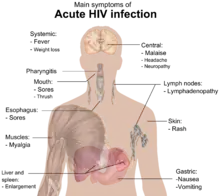

Main symptoms of acute HIV infection

During this period (usually days to weeks post-exposure) fifty to ninety percent of infected individuals develop an influenza or mononucleosis-like illness called acute HIV infection (or HIV prodrome),[2][3] the most common symptoms of which may include fever, lymphadenopathy, pharyngitis, rash, myalgia, malaise, mouth and esophageal sores, and may also include, but less commonly, headache, nausea and vomiting, fatigue, ulcers in the mouth or on the genitals, enlarged liver/spleen, weight loss, thrush, night sweats and diarrhea and neurological symptoms. Infected individuals may experience all, some, or none of these symptoms.[4] The duration of symptoms varies, averaging 28 days and usually lasts at least a week.[5]

Because of the nonspecific nature of these symptoms, they are often not recognized as signs of HIV infection. Even if patients go to their doctors or a hospital, they will often be misdiagnosed as having one of the more common infectious diseases with the same symptoms. As a consequence, these primary symptoms are not used to diagnose HIV infection, as they do not develop in all cases and because many are caused by other more common diseases. However, recognizing the syndrome can be important because the patient is much more infectious during this period.[6]